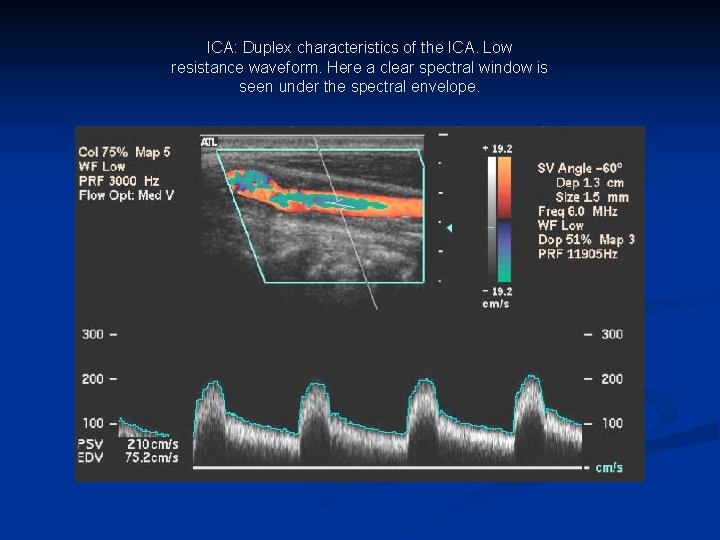

ICA: Duplex characteristics of the ICA. Low resistance waveform. Here a clear spectral window is seen under the spectral envelope.